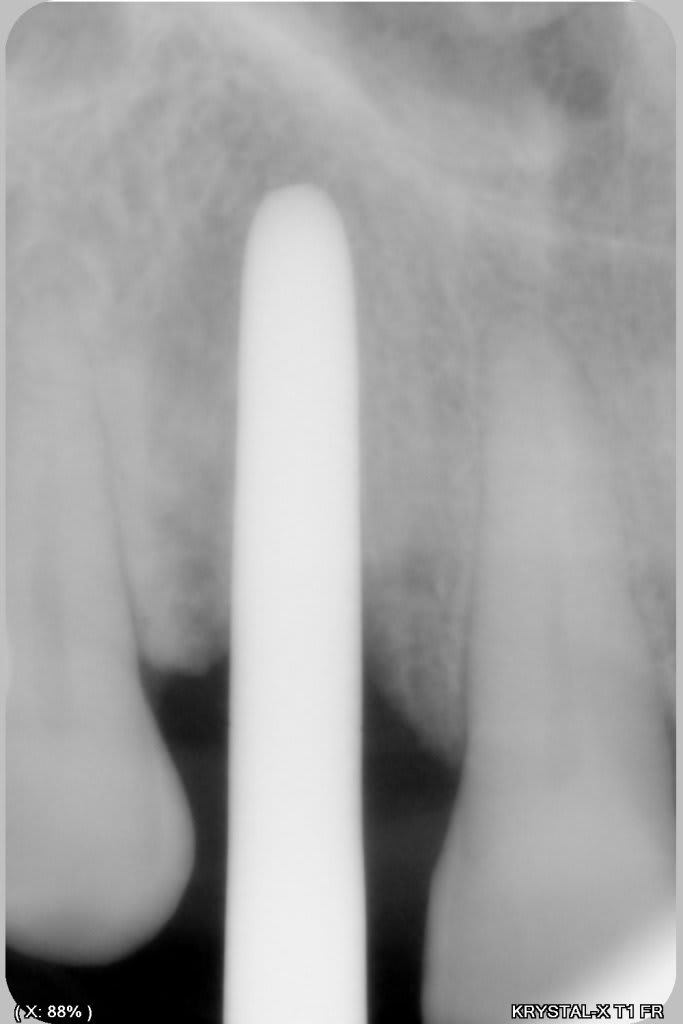

un petit cas comme j'aime, perte de 11, avec atteinte de la paroi vestibulaire.

Manipulation de la paroi palatine, afin de déplacer la moitié de l'os en vestibulaire, et pose d'un Px (Anthogyr) utilisation, de lame 11, ostéotome demi lune de Tatum, spreader (Meissinger) et divers.

Je n'ai jamais pratiqué l'expansion au bistouri, quelle est la technique?

Tu utilises la lame 11 comme un ciseau que tu tapes avec un maillet?

la lame (11 ou 15 suivant les cas) permet de ne pas consommer d'os, contrairement au piezzo par exemple.

Il faut travailler dans l'axe de l'os, en "tapotant" au maillet, en gardant à l'esprit que la lame est très cassante si on n'est pas dans l'axe du bistouri (j'ai eu une seule casse en 30 ans, mais c'est désagréable), ensuite pour la retirer, mouvement mesio distal, jamais vestibulo palatin.